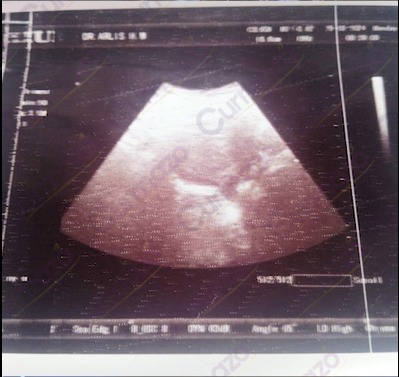

Saya nggak tau kalau gejala yang saya rasakan 1 tahun belakangan ini adalah ciri-ciri kista. Siklus haid saya tidak normal hanya berlangsung selama 3 hari, disertai gumpalan darah dan serabut-serabut kecil.

25 Agustus 2025, setelah pulang kerja badan saya rasanya capek sekali dan perut bagian bawah terasa nyeri, akhirnya saya pergi cek ke dokter kandungan. Saya kaget sama hasil USG nya. Ternyata saya ada 3 kista yang berukuran 5.59 cm, 4.68 cm, dan 5.23 cm. Disitu saya baru paham, ternyata gejala yang selama ini saya alami itu disebabkan oleh kista.

Foto hasil USG before:

Karena ukuran kistanya sudah besar jadi dokter menyarankan untuk dioperasi. Saya dengar kata operasi aja sudah parno duluan. Takut banget kalau sampai dioperasi, jadi saya cari pengobatan kista selain operasi di Facebook, keluar rekomendasi herbal Curmazo dan K-Muricata. Setelah baca-baca testi sudah banyak yang bisa pulih, saat itu juga saya langsung konsultasi dan pesan 1 paket.